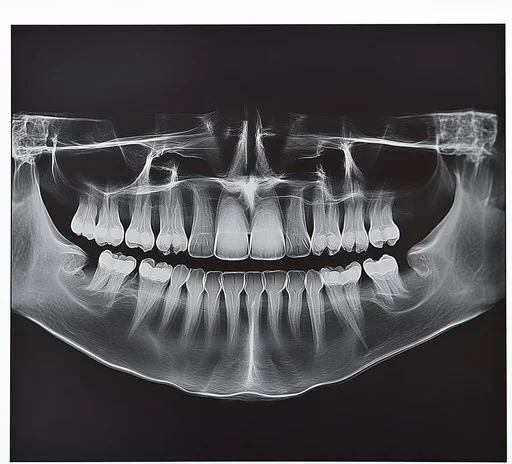

Panoramic Dental X-rays

This imaging captures the entire mouth, including jaws, sinuses, and wisdom teeth, in a single image.